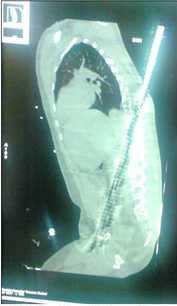

For one unnamed 22-year old Indian worker standing at the bottom of a tower seemed to be enough to get impaled on a 2.5M long and 18cm thick Iron rod. The rod apparently fell from the 25th floor of the building site and entered the victim from the back and exited from this pelvis.